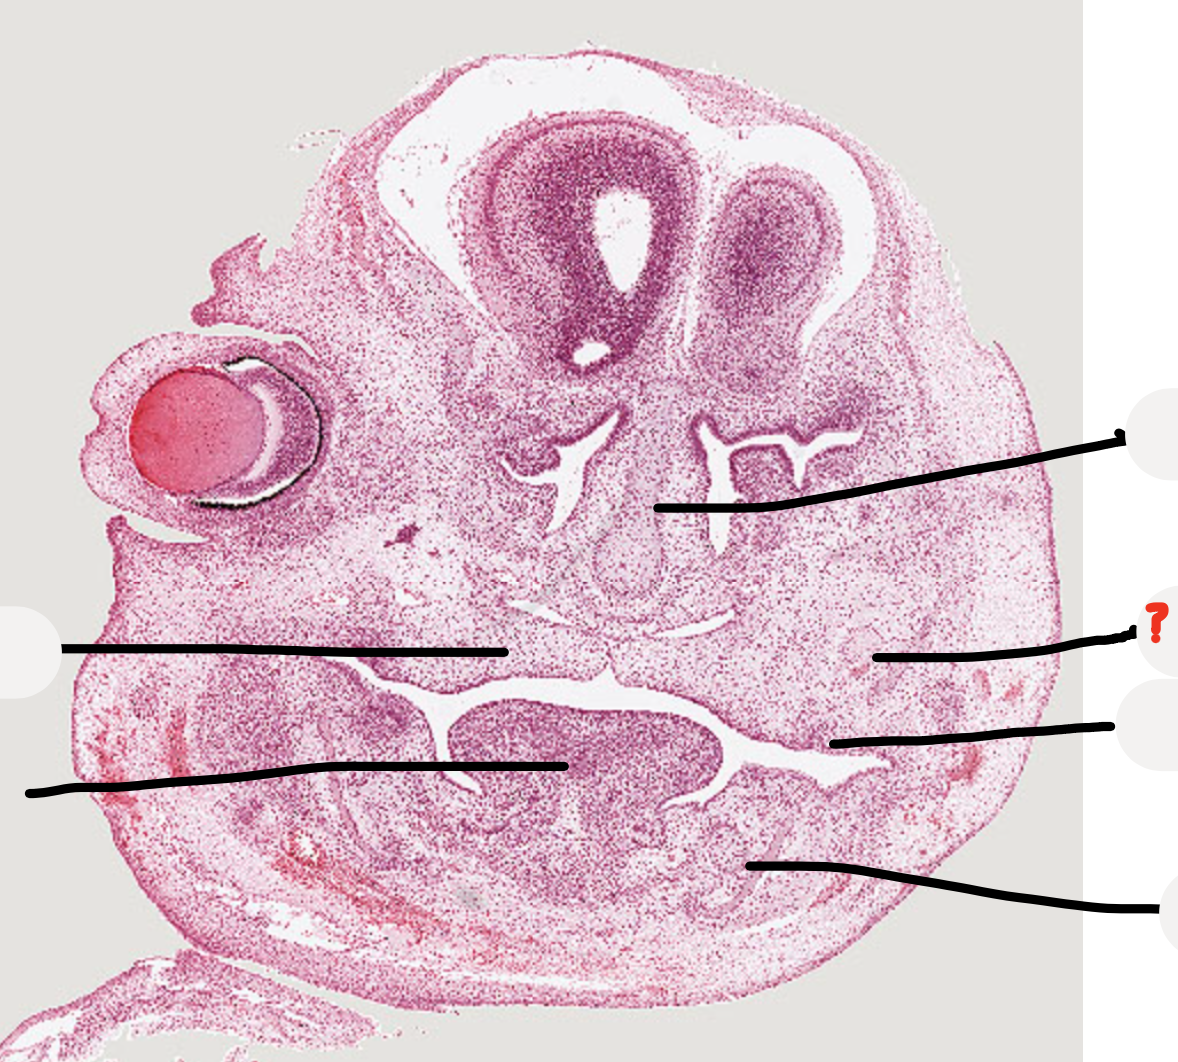

Q

what age is this specimen? why?

A

Week 8, palatal shelves elevated but not fused yet

which forms first maxilla or mandible?

24

mandibular process

meckel’s cartilage

25

developing mandible

26

what is this structure at the base of the nasal capsule?

developing vomer dark cells are osteoblasts making bone

30

tooth germ

31

maxillary nerve trunk

32

palatal shelves

33

34

meckel's cartilage